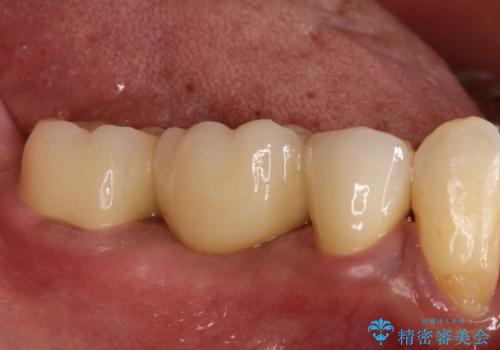

歯根の縦方向への破折は保存不可となることが多いです。

今回は抜歯後、オールセラミックにて修復を行うことで審美性の高い治療を行うことができました。